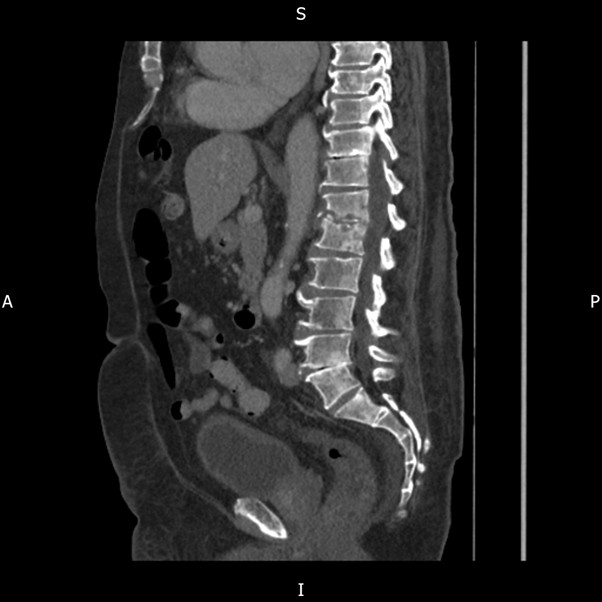

Cases of the Week

Check out our Cases of the Week!